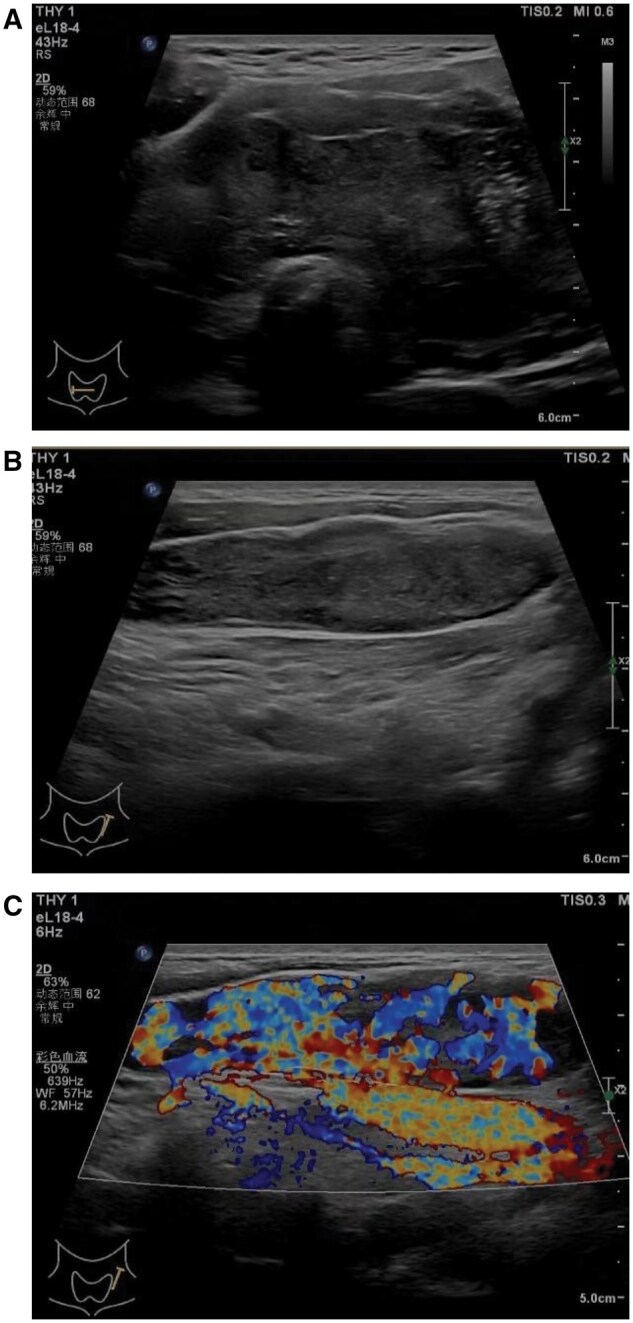

Anaplastic thyroid carcinoma (ATC) is a highly aggressive thyroid malignancy, comprising 1%-4% of thyroid cancers, with rapid local invasion and distant metastasis. We report a 57-year-old male with ATC presenting with a neck mass, hoarseness, and dysphagia. Imaging showed cancer thrombus in bilateral internal jugular veins, with a biopsy confirming ATC. This case highlights the imaging and pathological features of ATC and emphasizes the importance of ultrasound in evaluating intravascular cancer thrombus, aiding accurate diagnosis and management.

间变性甲状腺癌(ATC)是一种高度侵袭性的甲状腺恶性肿瘤,占甲状腺癌的1%-4%,具有快速的局部侵袭和远处转移。我们报告一位57岁男性ATC患者,表现为颈部肿块、声音嘶哑和吞咽困难。影像显示双侧颈内静脉癌栓,活检证实为ATC。本病例强调了ATC的影像学和病理特征,强调了超声在评估血管内癌血栓,帮助准确诊断和治疗中的重要性。